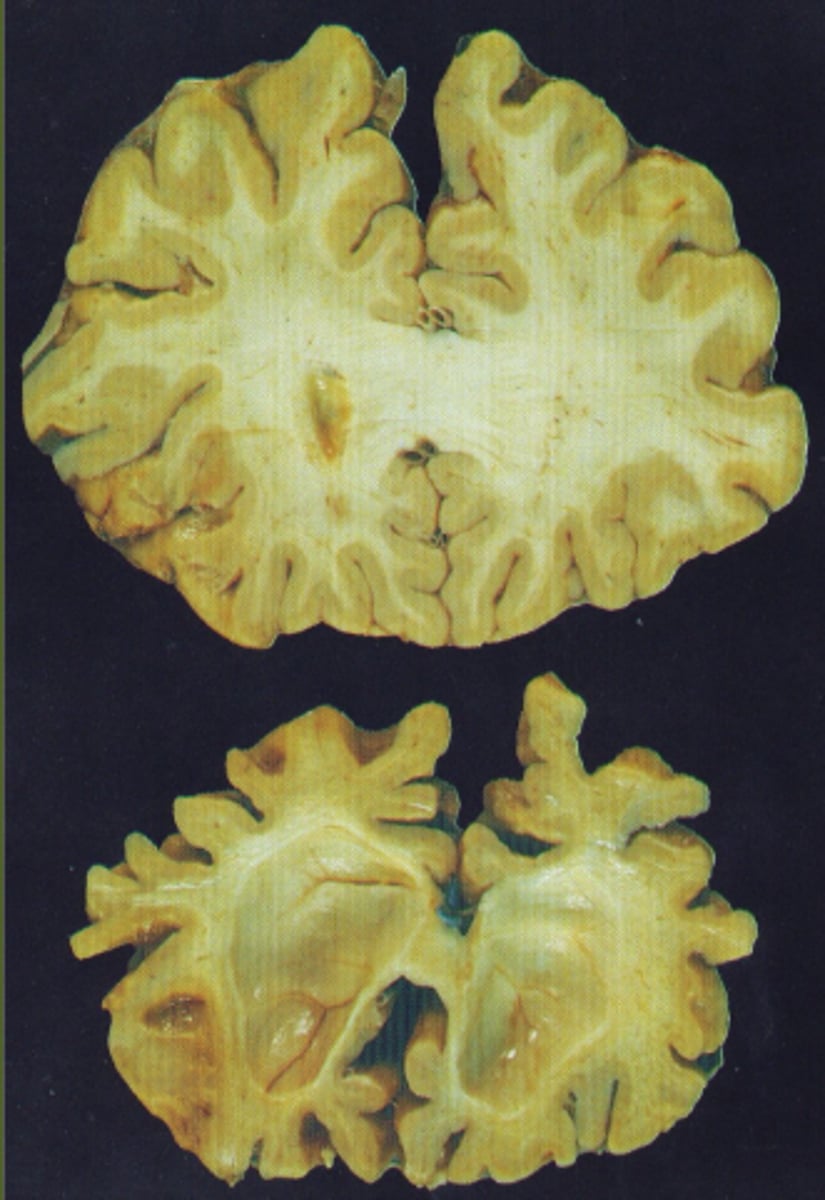

Dementia

An umbrella term for a collection of symptoms that fit the description of multiple conditions that result in changes to the brain

What structural changes in the brain are occurring with dementia?

Cells are shrinking and dying

4 Truths of Dementia

1. At least two parts of the brain are dying